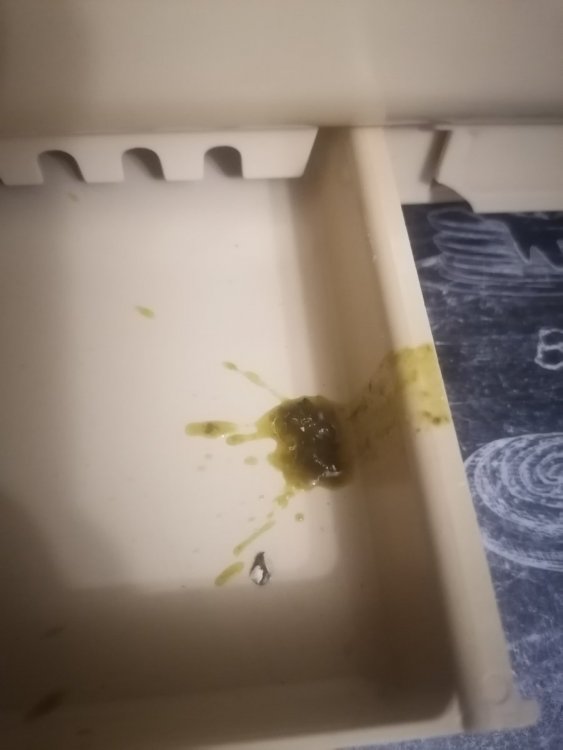

Здравствуйте, помогите, пожалуйста. Орнитолога у нас поблизости нет, ветеринары разводят руками и помочь не могут, не понимают они в птицах. у нас болеет самка волнистого попугая. Взяли её ещё летом, была совсем маленькая. Много спала, думали, что просто мелкая ещё. Стул всё время был неоформленный, много белого в помёте. Мальчик у нас какает прям улиточками, а самка жидким. В последний месяцы так вообще поносит. Всё время хохлится и спит. Посадила в клетку, до этого были на свободе. Давала дорин пару дней, стул стал чёрным, перестала давать. Сейчас в поилку добавляю Ветом 1. Дня три уже пьёт, сегодня помёт снова почернел. Она кушает, аппетит есть. Камень в клетке, купила еще глиняный камень. Вокруг клоаки перьев нет у неё и не было, всё время воспаленная кожа. Ещё смущает то, что восковица у неё стала голубого цвета, возраст примерно месяцев 7-8. Пока была на воле самец постоянно её кормил, прям закармливал, может это усугубило. Подскажите, пожалуйста, чем её лечить. К орнитологу попасть нет возможности. Приложила фото сегодняшнего помёта. До этого был жидкий и очень много. А сегодня прям чёрный какой то.